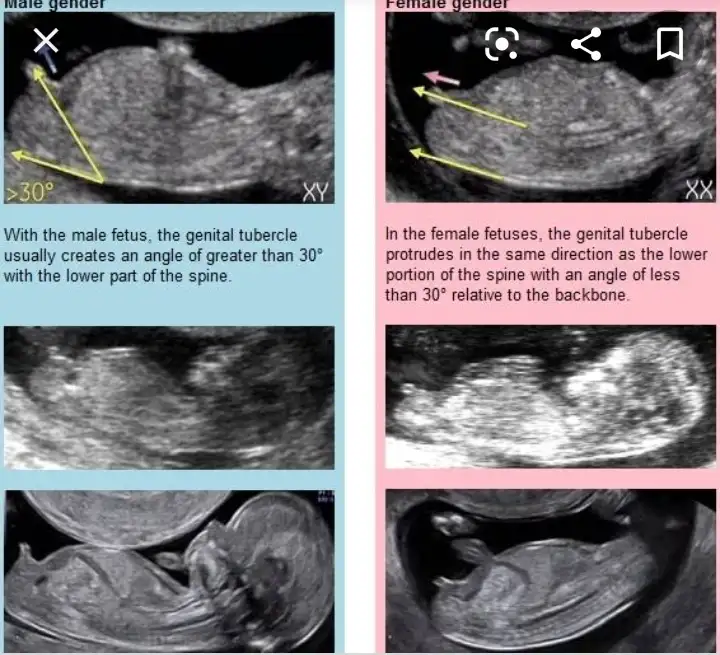

Nub teorisi ne göre özel bölge duzse kız yukarı bakıyorsa erkekValla nasıl anlıyonuz ya çıldırcam

Şu çıkıntı karşıya bakıyorsa kız yukarı doğruysa hafiften erkekk deniyorNasıl anlıyorsunuz kizlar

Kızlar tam olarak buben kızımdayken bilmiyordum fakat geriye dönük ultrason goruntusune baktım gecen nub tutmus :)